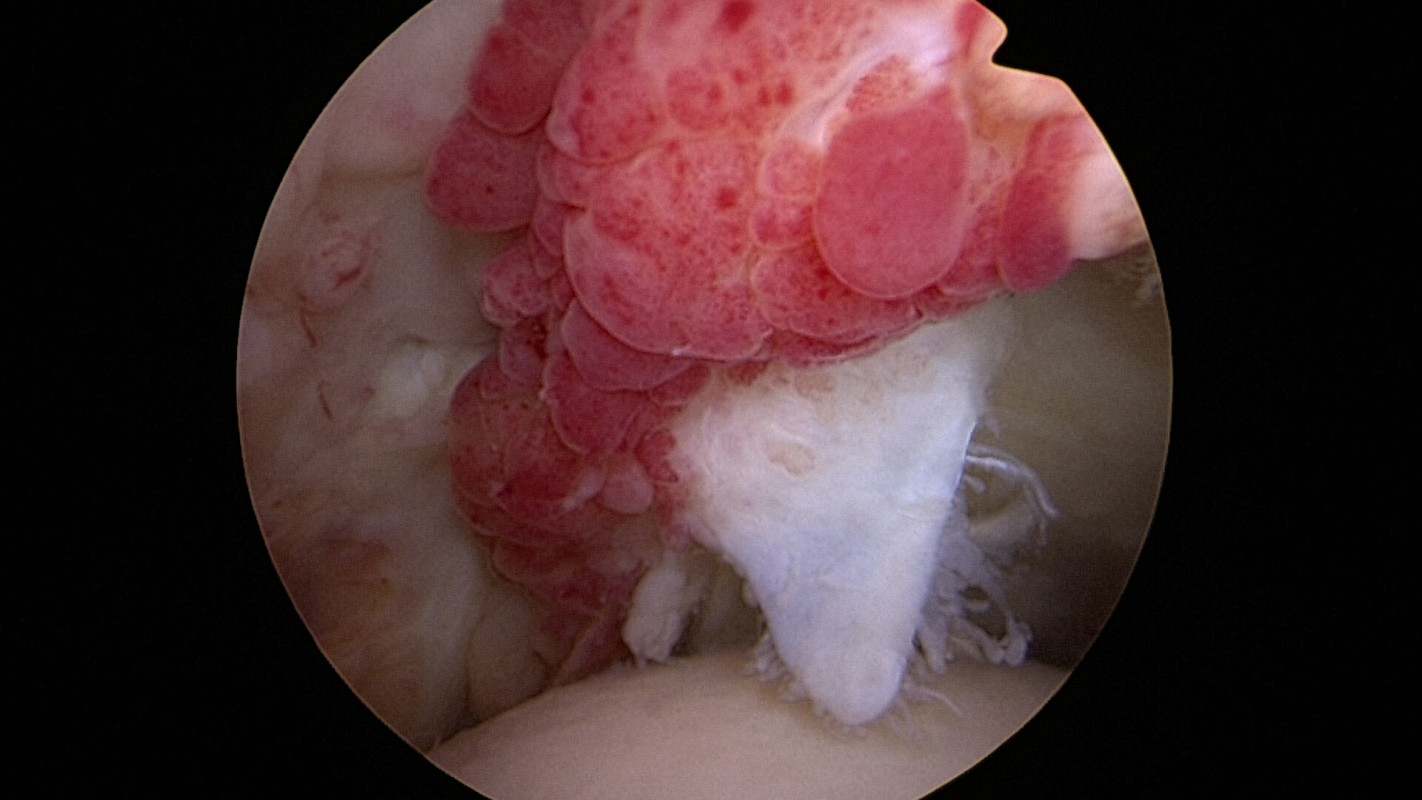

fig 5. calcification exubérante

L’ablation de calcifications : parfois la tendinopathie s’accompagne de dépôts calcaires qui sont douloureux. En cas d’échec du traitement médical leur ablation devient nécessaire. Une rupture peut faire suite à cette ablation quand la calcification est volumineuse. Elle sera réparée immédiatement.